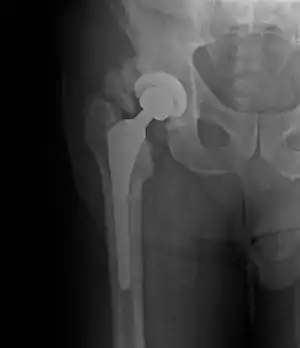

| Heterotopic ossification around the hip joint in a patient who has undergone hip arthroplasty |

Heterotopic ossification of varying severity can be caused by surgery or trauma to the hips and legs. About every third patient who has total hip arthroplasty (joint replacement) or a severe fracture of the long bones of the lower leg will develop heterotopic ossification, but is uncommonly symptomatic. Between 50% and 90% of patients who developed heterotopic ossification following a previous hip arthroplasty will develop additional heterotopic ossification.

Heterotopic ossification often develops in patients with traumatic brain or spinal cord injuries, other severe neurologic disorders or severe burns, most commonly around the hips. The mechanism is unknown. This may account for the clinical impression that traumatic brain injuries cause accelerated fracture healing.[1]